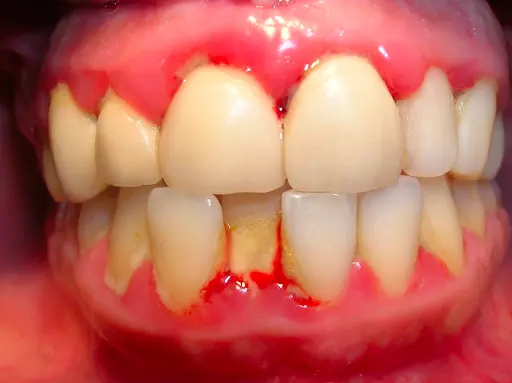

Viêm nha chu là tình trạng mà nướu xung quanh răng trở nên sưng, đỏ có thể gây ra chảy máu khi đánh răng, xương xung quanh răng cũng bị tiêu đi làm răng trở nên lung lay ở nhiều mức độ khác nhau. Trường hợp bị  viêm nha chu  nặng sẽ khiến mô nướu và xương bị tổn thương nghiêm trọng, răng sẽ trở nên lung lay thậm chí có thể mất răng nếu không điều trị kịp thời.

• Nướu trở nên sưng và có thể mềm khi chạm. Nướu bình thường có màu hồng nhạt. Trong trường hợp viêm nướu, chúng có thể trở nên đỏ, thậm chí có thể chuyển sang màu đỏ đậm.

• Một trong những dấu hiệu rõ ràng nhất của viêm nướu là chảy máu nướu khi đánh răng hoặc sử dụng chỉ nha khoa.

• Mảng bám răng và cao răng bám trên bề mặt răng, nhất là vùng cổ răng.